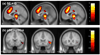

Error detection and behavioral adjustment are core components of cognitive control. Numerous studies have focused on the anterior cingulate cortex (ACC) as a critical locus of this executive function. Our previous work showed greater activation in the dorsal ACC and subcortical structures during error detection, and activation in the ventrolateral prefrontal cortex (VLPFC) during post-error slowing (PES) in a stop signal task (SST). However, the extent of error-related cortical or subcortical activation across subjects was not correlated with VLPFC activity during PES. So then, what causes VLPFC activation during PES? To address this question, we employed Granger causality mapping (GCM) and identified regions that Granger caused VLPFC activation in 54 adults performing the SST during fMRI. These brain regions, including the supplementary motor area (SMA), cerebellum, a pontine region, and medial thalamus, represent potential targets responding to errors in a way that could influence VLPFC activation. In confirmation of this hypothesis, the error-related activity of these regions correlated with VLPFC activation during PES, with the cerebellum showing the strongest association. The finding that cerebellar activation Granger causes prefrontal activity during behavioral adjustment supports a cerebellar function in cognitive control. Furthermore, multivariate GCA described the "flow of information" across these brain regions. Through connectivity with the thalamus and SMA, the cerebellum mediates error and post-error processing in accord with known anatomical projections. Taken together, these new findings highlight the role of the cerebello-thalamo-cortical pathway in an executive function that has heretofore largely been ascribed to the anterior cingulate-prefrontal cortical circuit.